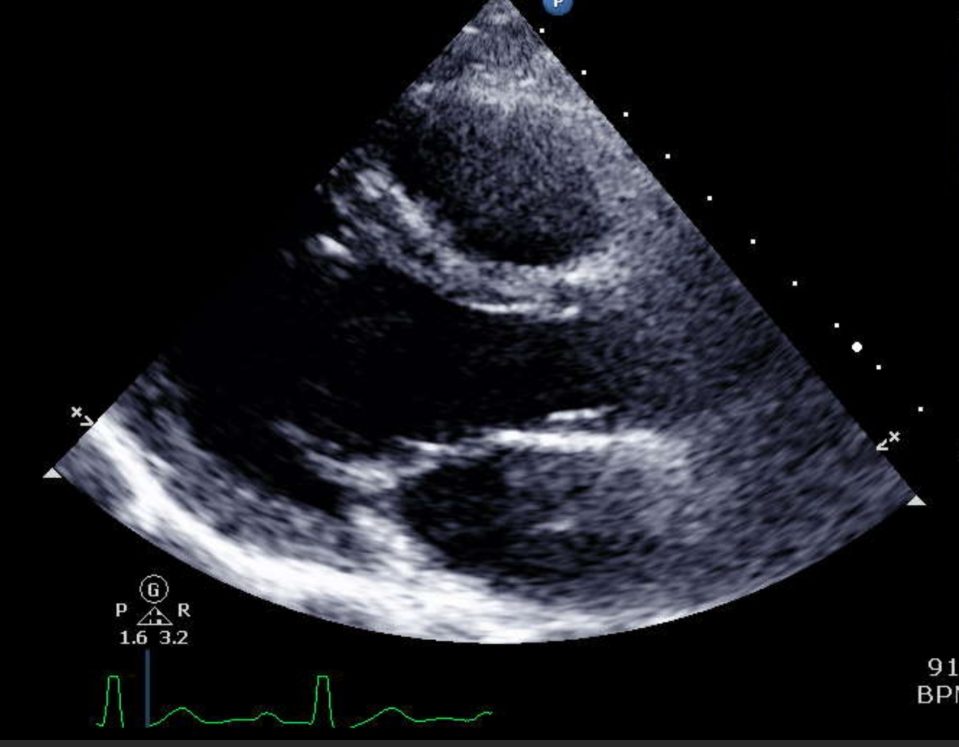

Stress Echocardiograms

Both treadmill and dobutamine options available for accurate evaluations.

Transesophageal Echocardiograms

In-depth assessments through minimally invasive procedures.